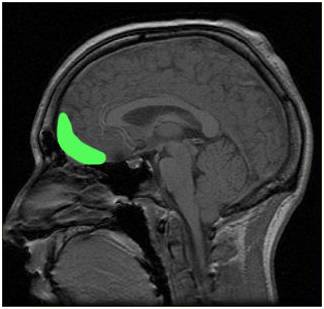

抑郁症与大脑两个区域功能性传递增加有关

之前发表在“大脑”期刊上的一项研究发现,抑郁症与大脑两个区域功能性传递增加有关,其中之一是和没有得到奖励和遭受惩罚区域有关(外侧眶额叶皮层),另一个是和自我意识区域有关(前颞骨)。

研究中,909人(421个重症抑郁障碍患者和488个对照组)接受了先进的MRI神经成像技术大脑扫描。

此外,研究人员发现,重度抑郁发作与内侧OFC的奖励中心和大脑其他记忆系统之间的功能性传递降低有关。这就解释了为什么患有临床抑郁症的人难以回忆起之前快乐的记忆。